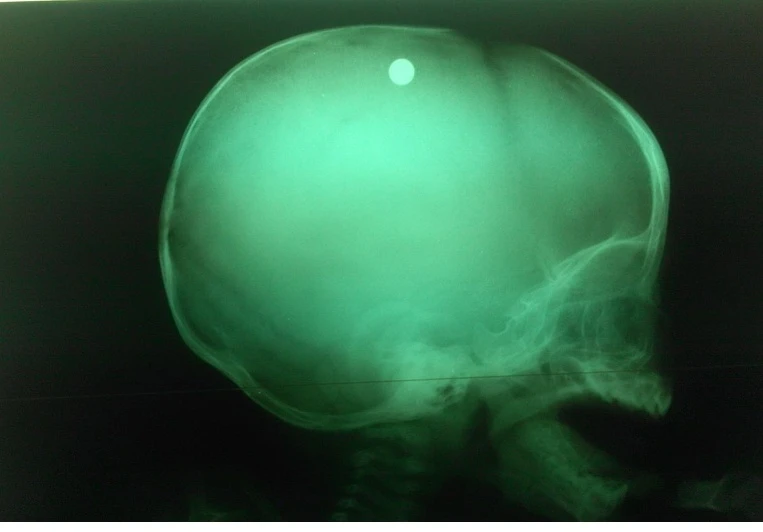

Các bác sĩ xác định đây là 1 trường hợp vết thương sọ não cần phẫu thuật gấp vì phim chụp XQ sọ cho thấy viên đạn vẫn còn nằm trong sọ của bé. Bé nhanh chóng được hồi sức, chụp thêm CTscan sọ não và được đưa vào phòng mổ. Sau 5 tiếng phẫu thuật, các bác sĩ đã gắp ra được đầu đạn tròn, đường kính khoảng 1cm, hơi bị dẹp ở đầu.

Bác sĩ Đặng Xuân Vinh, phó khoa ngoại thần kinh, BV Nhi đồng 2 cho biết vị trí dị vật (viên bi sắt) nằm trong nhu mô não (cách xương sọ 2cm). Đạn được bắn thẳng vào não. Đường đi của viên đạn này từ chẩm trái xuyên qua xương sọ vào nhu mô não, rồi lên đỉnh trái, cuối cùng chuyển hướng sang đỉnh phải đầu. Vì thế nhu mô não của bệnh nhi này bị tàn phá nặng, kèm xuất huyết não.